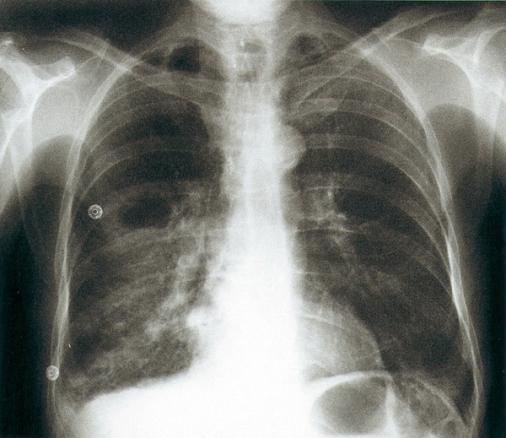

Radiographie de thorax de face. Pneumonie abcédée d'inhalation, axillaire droite chez un porteur d'un cancer ORL traité par chirurgie et radiothérapie.